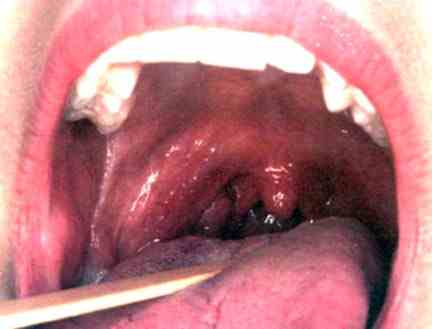

5. Teeth and Gums. When you view our illustrations and the brains close proximity to the key lymph nodes you will easily see how healthy teeth and gums play a part in the devil's workshop.

I think the first thing to do in this feature it to ask you a couple of simple questions. How close are the teeth and gums to your brain? How close are the teeth and gums to the garbage cans, the lymph nodes in your neck and under your chin? 1/4 of an inch, a 1/2 an inch?

It

has been known for many years that diseased gums were directly related to heart

disease. My Dad died of esophagus cancer and I would bet my life his

neglected teeth and gums were at least partially responsible. He died a

horrible death. Inflammation plugging up the lymph glands is a no brainer

and the Devil just adores fools that neglect their teeth and gums.

Depriving the glands of doing its job by neglect is just plain stupid.

Diseased gums are most always accompanied by bleeding gums and you talk about a gateway to the blood net work, there are few gateways but this is one. Bacteria in the mouth is abundant, but it doesn't belong in your bloodstream. You have bleeding gums don't walk to a good Periodontist run as fast as you can.